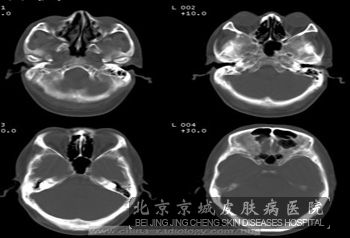

推荐阅读:结节硬化症的脑部病变